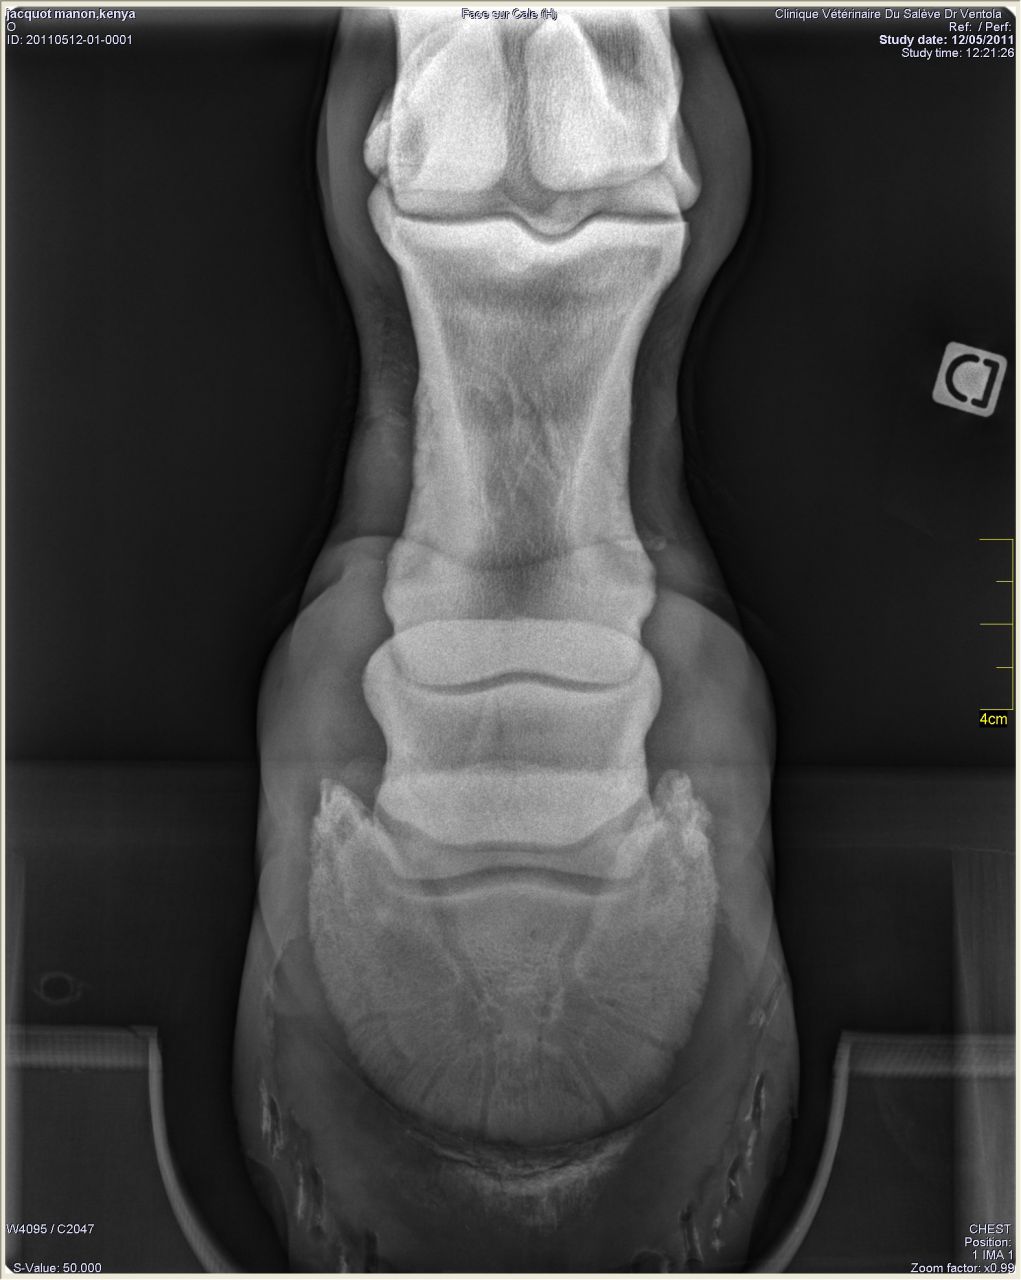

| Dire merci | Donc les radios: Antérieur gauche de profil où on peut voir le petit bout d'os au somment entre les phalanges 2 et 3 ![]() On peut noter un autre souci: normalement le milieu de la 2ème phalange doit être aligner avec le milieu du pied (c'est ce que représente le trait vertical marqué 77mm). Or ici le pied est à 2/3 devant. Ce qui a un effet levier et fatigue donc les tendons de la jument. Le pied gauche de face à plat: ![]() On peut remarquer que la 1ère phalange n'est pas nette (le véto m'a dit qu'on dirait une radio d'un cheval de 20ans.... :/) Le pied gauche de face en extension: ![]() |